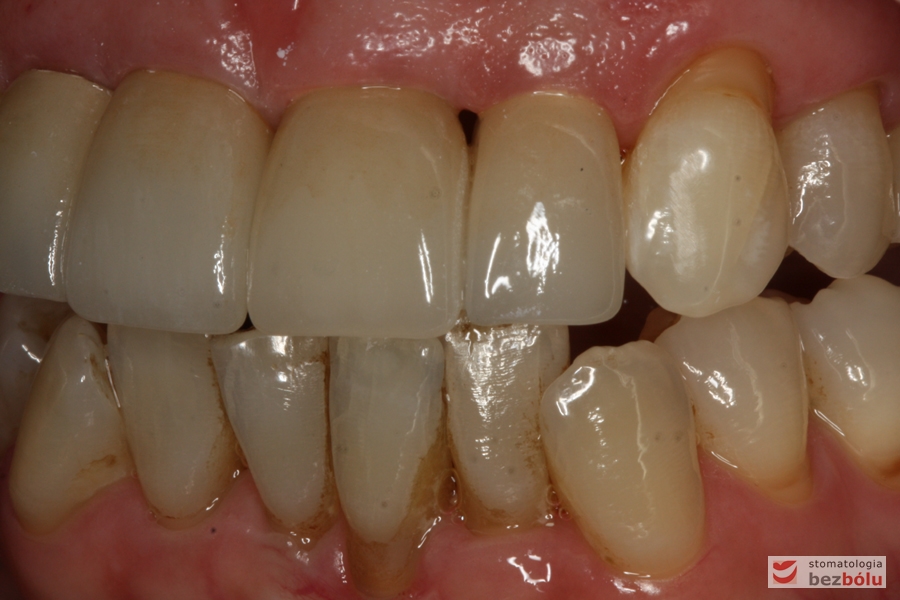

Zęby w zwarciu - widok frontalny, zgryz krzyżowy w pozycji kłów, paradontalny status siekaczy

Zęby w zwarciu – widok frontalny, zgryz krzyżowy w pozycji kłów, paradontalny status siekaczy